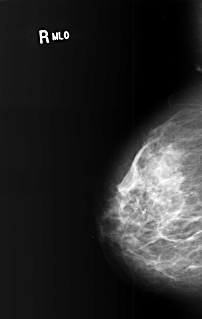

B_3400_1.RIGHT_MLO

RIGHT_MLO LINES 5104 PIXELS_PER_LINE 3232 BITS_PER_PIXEL 12 RESOLUTION 50 NON_OVERLAY